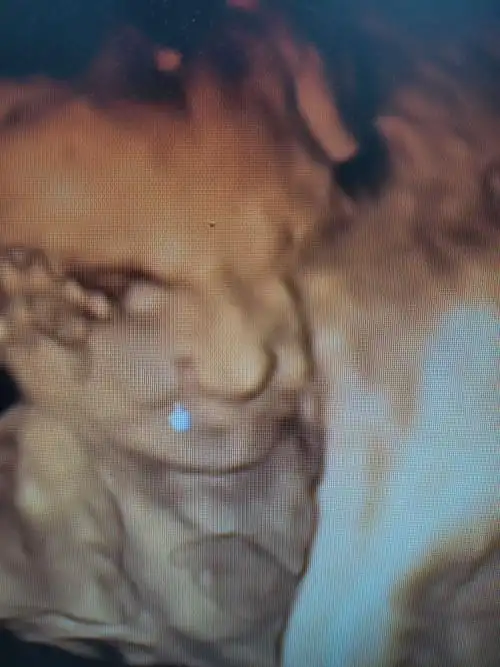

请各位宝妈帮我看一下这个四维是兔唇吗?

四维照片宝宝这样算兔唇吗

是唇裂吗?有出生结果